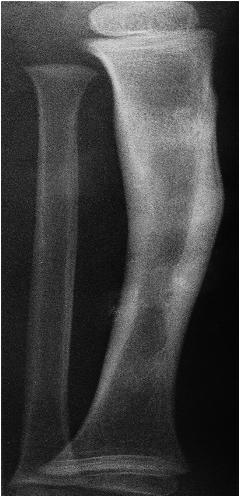

It may be thick and irregular but shows the same homogeneous density as does the normal cortex. The causes include chronic Osteomyelitis & healed trauma.

Cortical thickening

in the midshaft of the tibia from old, healed Osteomyelitis